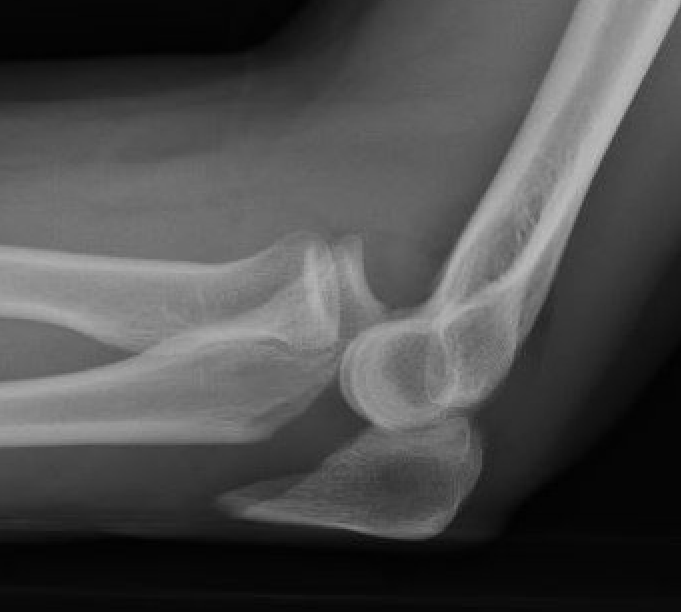

Simple Monteggia fracture - dislocations

Definition

Proximal ulna / olecranon fracture

- posterior radial head dislocation most common in adults

- no fractures

Bado Type II most common in adults with posterior radial head dislocation